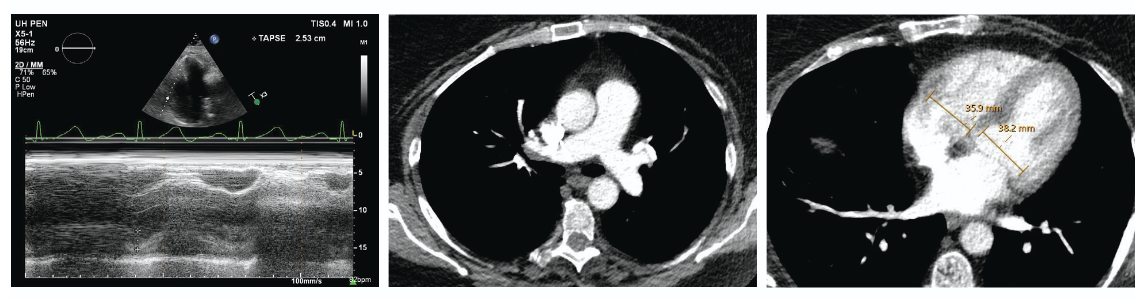

Imaging revealed bilateral PE with a saddle component obstructing flow in the pulmonary arteries, with a right ventricular to left ventricular (RV/LV) ratio of 2.39, indicating severe strain on the heart (Figure 2). The patient was screened and subsequently enrolled in the AVENTUS IDE clinical study.

Figure 5. Subsequent echocardiogram showed preserved RV ejection, with normal tricuspid annular plane systolic excursion (TAPSE). Follow-up CT scan, performed within 48 hours for study protocol, showed resolution of thrombus and a normalized RV/LV ratio of < 1.

respectively. The patient’s RV/LV ratio normalized to 0.94, demonstrating rapid reversal of RV dilation and strain (Figure 5). These results highlight the AVENTUS system’s potential to efficiently reduce thrombus burden and improve hemodynamic parameters in patients with PE.